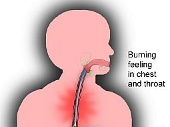

₦28,000.00Heart Burn - Treat the painful burning feeling in your chest or throat. Burning sensation in the esophagus.